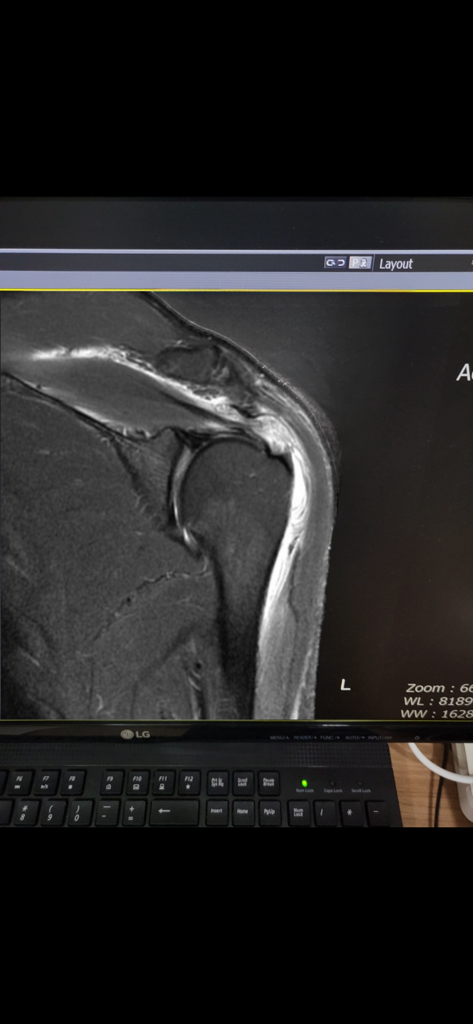

회전근개 파열 mri 봐주세요

어깨 회전근개 파열로 mri 찍었는데요

수술을 해야하는지

주사맞으면서 보존차료해야할지

못정하겠습니다

사진보고 의견 부탁드립니다..!

• 1번 째 사진

올려주신 사진상 회전근 (SST) 파열이 의심되는데, 한장만 올려주셔서 정확히 파악하기에 무리가 있습니다.

MRI를 처방한 병원에서 판독이 나왔을테니 판독소견서를 참고하시고 치료방침은 정형외과 전문의와 상담해보시는걸 추천드립니다.